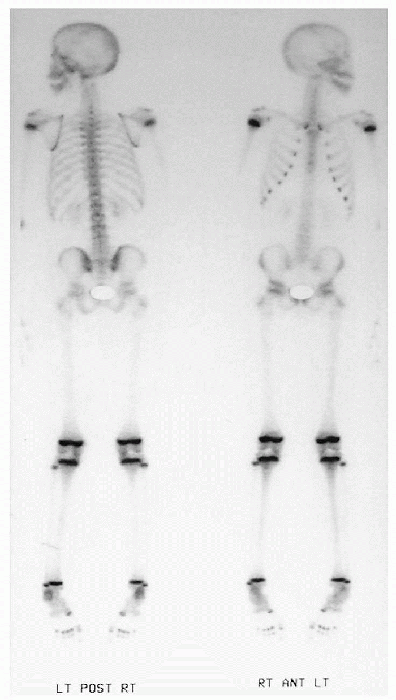

Figure 32-4

Normal radionuclide bone scan of the whole body. Note the increased uptake of isotope at the growth plates that can mask subtle abnormalities. |

Bone scintigraphy is performed by

administering a radioisotope intravenously followed by imaging of the

musculoskeletal compartment with a gamma camera.-

□ The most commonly used agents for bone

scintigraphy are the technetium-labeled phosphate analogs that become

incorporated into the bone.

Causes of abnormally increased isotope activity include increased blood flow and bone turnover.

-

Causes of abnormally diminished or absent

uptake include bone infarction, aggressive infection, or high

intracapsular pressures due to large joint effusions. -

A SPECT scan

(single photon emission computed tomography) differs from routine

two-dimensional planar images in that it allows improved image contrast

by removing overlying structures that may interfere with image

interpretation.-

□ As with conventional cross-sectional

imaging modalities such as CT and MRI, images are presented as “slices”

in axial, coronal and sagittal planes, or as a three-dimensional (3D)

rotating image. -

□ SPECT studies are especially useful in the evaluation of suspected vertebral or rib abnormalities.

Bone scintigraphy has been used in the initial evaluation of nonaccidental injury.

□ Its strength lies in the discovery of old, near completely healed rib fractures.

□ The major limitation of bone

scintigraphy is its inability to recognize subtle metaphyseal injuries

in the presence of normal “hot” growth plates.